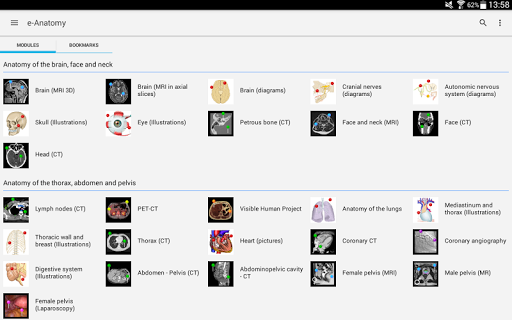

IMAIOS e-Anatomy adalah atlas anatomi manusia untuk dokter, ahli radiologi, mahasiswa kedokteran, dan teknisi radiologi. Dapatkan cuplikan lebih dari 26.000 gambar medis dan anatomi secara gratis sebelum berlangganan atlas anatomi manusia terperinci kami.

e-Anatomy didasarkan pada atlas daring IMAIOS e-Anatomy yang telah memenangkan penghargaan. Bawalah referensi anatomi manusia terlengkap, ke mana pun Anda pergi, di perangkat seluler atau tablet Anda.

e-Anatomy memiliki lebih dari 26.000 gambar yang berisi serangkaian gambar dalam tampilan aksial, koronal, dan sagital serta radiografi, angiografi, gambar diseksi, bagan anatomi, dan ilustrasi. Semua gambar medis diberi label dengan cermat, lebih dari 967.000 label tersedia dalam 12 bahasa termasuk Terminologia Anatomica Latin.